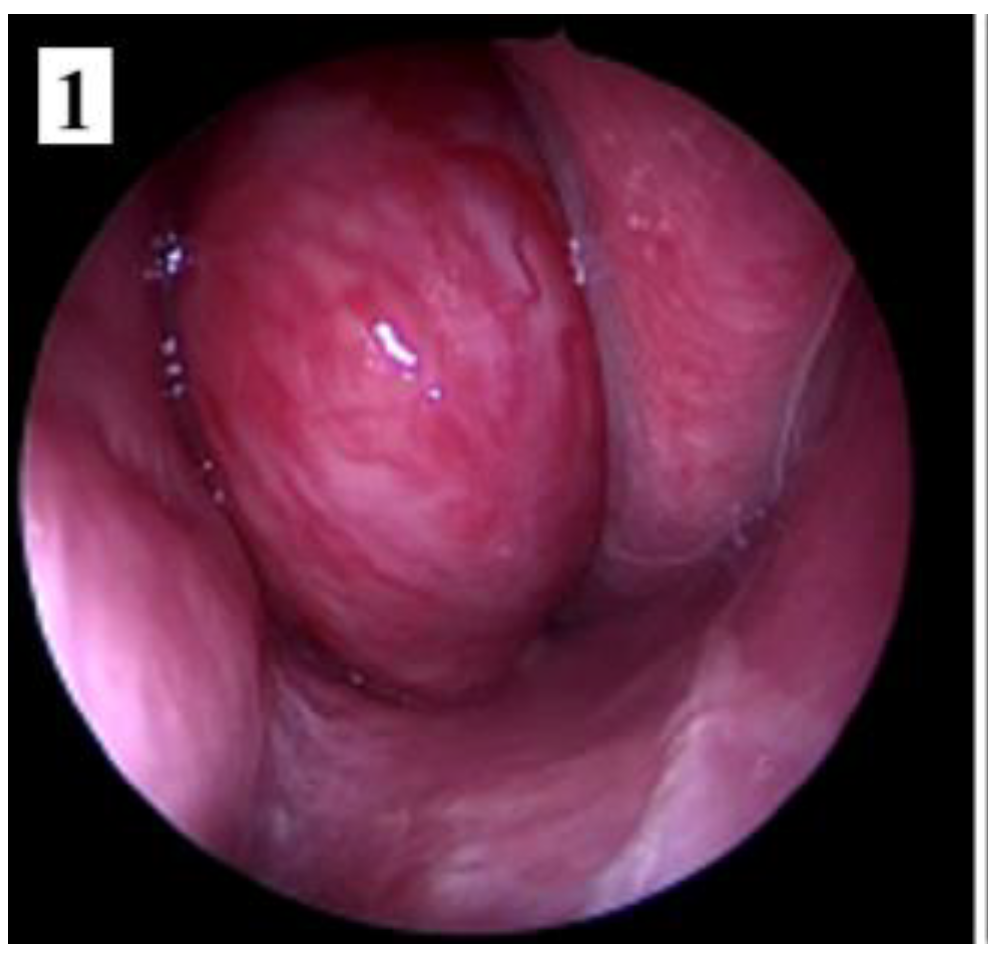

Management of stage IIC cases, with extension into the infratemporal fossa or extension posteriorly to the pterygoid plates, can be done by transnasal approach alone or by a combined approach. Preoperative embolization is mandatory for identifying the vascular feeding source and reducing intraoperative bleeding.

Figure 7. Preoperative MRI of a stage IIC juvenile angiofibroma. The Holman-Miller sign (the anterior bowing of the posterior maxillary wall) on the CT scan (part 1).